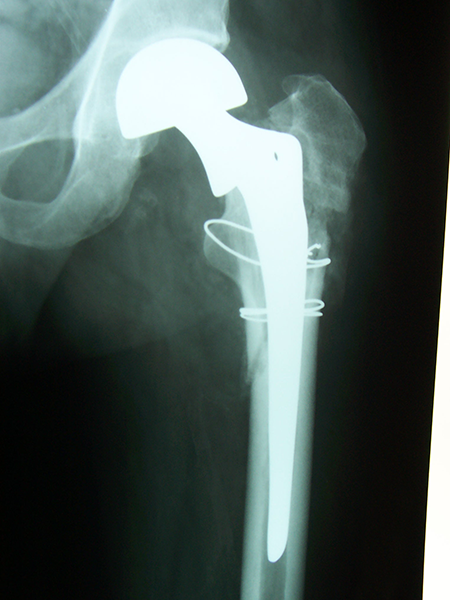

Case:7 Fracture Neck Femur with Implant failure and Re-Fixation with hemi-arthroplasty

Alcoholic Gardener by profession had slipped in bathroom & fell. He sustained fracture neck femur.He was operated with closed reduction & CC Screw fixation under IITV. Two weeks’ post fixation he again fell & sustained fracture in sub trochanteric region. He was treated with Hem-Arthroplasty with Tension band wiring.

Pre-Op

Post-Op

Post Fall

Oblique-Post Fall